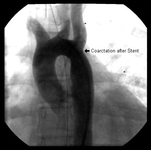

Angiography in the ascending aorta shows a focal area of narrowing after the left subclavian artery

From the personal collection of Jeffrey Gossett, MD, Children's Memorial Hospital, Northwestern University, Chicago; used with permission

After stent placement, the narrowed area is markedly improved